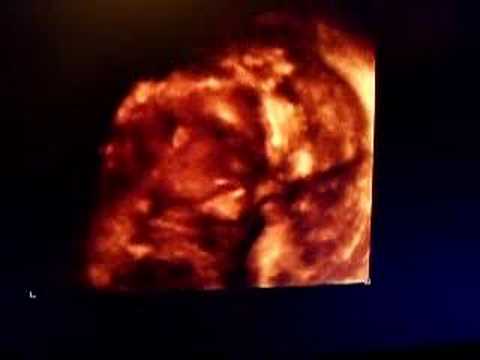

Had our 3D ultrasound of baby girl this week (ADORABLE!), 26 WEEKS PREGNANT! 3D ULTRASOUND AND!!! Just Our Life So Far. Subscribe Subscribed Unsubscribe 1,954 1K. HOW BABY GROWS IN THE WOMB DURING PREGNANCY - How TWINS are made? (Triples, Quads) - Duration: ... View Video

BABY 3D ULTRASOUND AT 28 WEEKS PREGNANT! - DAILY VLOG 459 ...

BABY 3D ULTRASOUND AT 28 WEEKS PREGNANT! 3D ultrasound 25 weeks, 4D view of baby, 25 week pregnancy, baby girl, first view - Duration: 14:46. Elena Elizabeth Wormington 1,232,674 views. 14:46 ... View Video

12 Weeks pregnant ultrasound , 3D / 12 Wochen Schwanger ...

12 weeks pregnancy The placenta is now well developed and doing its all important work in providing oxygen and nutrients to your growing baby and removing waste products from your baby’s blood.At 12 weeks pregnant your baby’s skeleton is currently made of cartilage (like you’d ... View Video